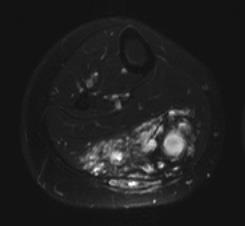

儿童静脉畸形的分类和硬化影响[1] ![]() III 和IV型静脉畸形的栓塞比较 I 和 II型静脉畸形栓塞高度危险